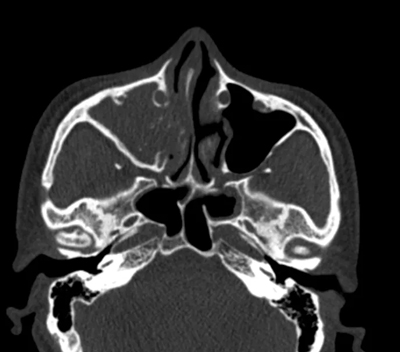

胡少爭主任為他進(jìn)行了

細(xì)致的鼻內(nèi)窺鏡檢查

還做了副鼻竇CT平掃檢查

結(jié)果發(fā)現(xiàn)

高大哥的右側(cè)上頜竇內(nèi)

有一個幾乎把整個竇腔

都填滿的大團(tuán)塊

大小跟乒乓球差不多